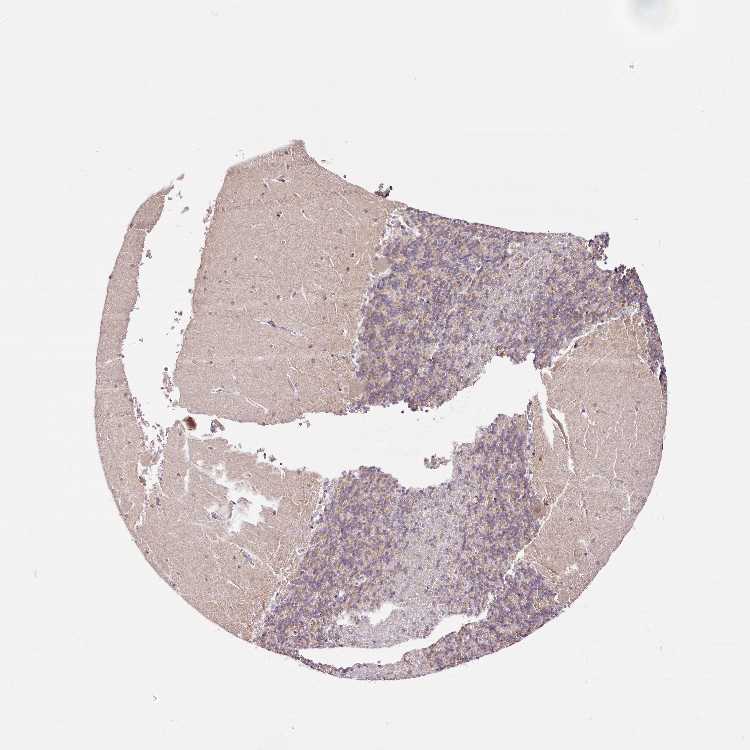

CEREBELLUM - Antibody stainingi

Antibody staining in the annotated cell types in the current human tissue is reported as not detected, low, medium, or high, based on conventional immunohistochemistry profiling in selected tissues. This score is based on the combination of the staining intensity and fraction of stained cells.

Each image is clickable and will lead to virtual microscopy that enables deeper exploration of all samples and also displays staining intensity scores, fraction scores and subcellular localization as well as patient and tissue information for each sample.

Antibody HPA037570

Purkinje cells High

Cells in granular layer Low

Cells in molecular layer Low